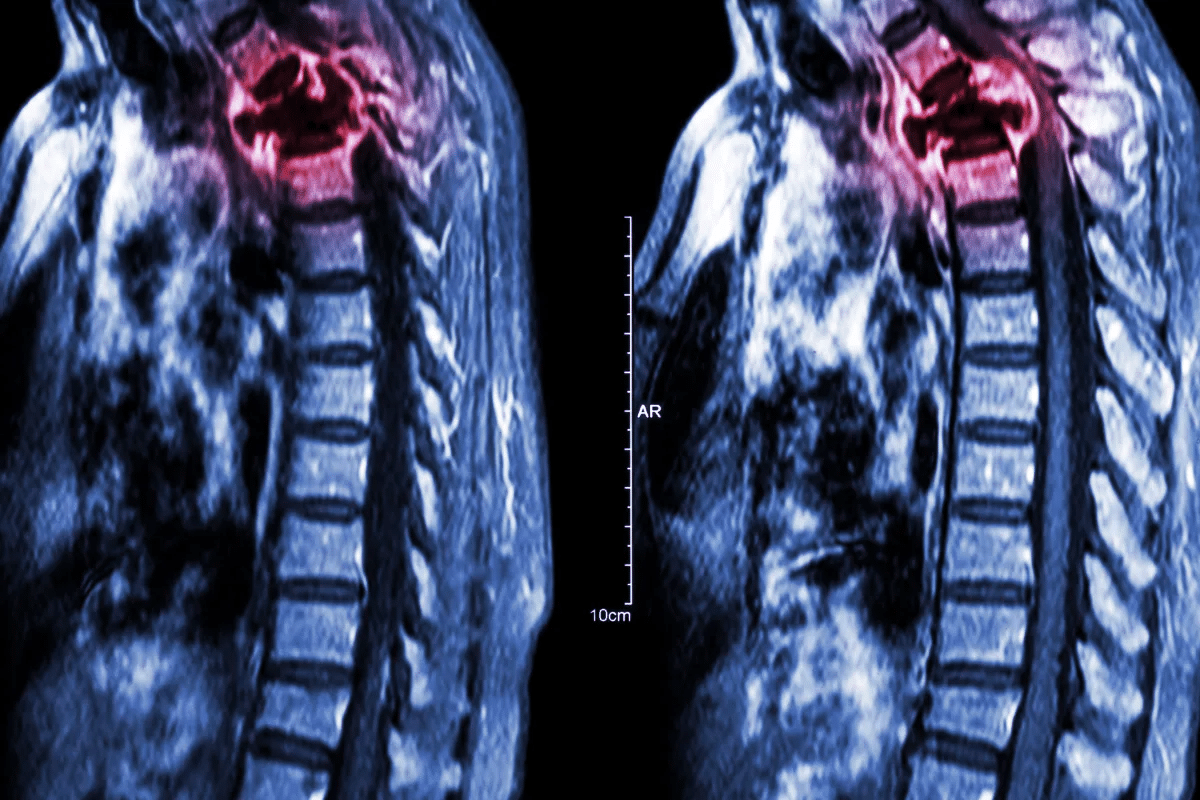

MRI is top-notch for checking soft tissue and bone marrow changes in bone cancer. It shows soft tissues clearly, helping doctors see how big the tumor is and if it’s near other structures. MRI is key for spotting bone marrow and soft tissue parts of bone tumors.

When symptoms show up, we start looking at the bone with imaging. We use different methods to see the bone and find any problems. These include:

MRI |

Looks at soft tissues and bone marrow |